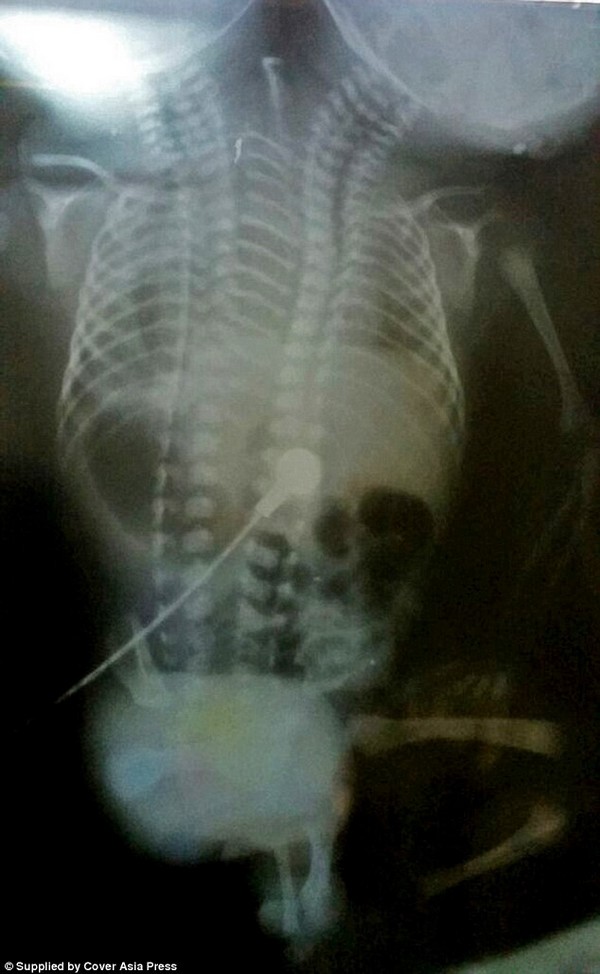

Mặc dù bề ngoài đứa trẻ có 2 đầu và một phần thân nhưng phim chụp X-quang cho thấy phần xương và các cơ quan nội tạng bên trong được tách rời. Các bác sĩ đã cân nhắc đến khả năng thực hiện phẫu thuật để tách rời 2 đứa trẻ nhưng ca dính liền quá phức tạp nên khả năng này là rất khó.

“Các ca phẫu thuật có thể được thực hiện trong một số ca sinh đôi dính liền, nhưng trường hợp này quá phức tạp và gần như không thể phẫu thuật”, bác sĩ Jai cho biết. “Mặc dù cặp sinh đôi có đầy đủ cơ quan nội tạng tách rời nhưng chúng đều dính liền bên trong một cơ thể, với chỉ 2 chân và 2 tay”.